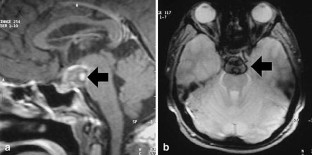

Brucellosis is a multisystem disease that may present with a large spectrum of clinical manifestations. Only five cases of intracranial aneurysm formation and/or subarachnoidal hemorrhage associated with brucellosis have been reported. In this paper, we take the opportunity to review these reports and present a new case of basilar artery aneurysm and subarachnoidal hemorrhage due to brucellosis.

Fig. 1